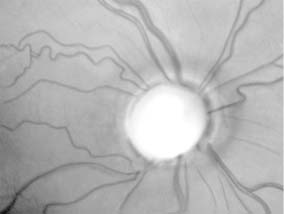

Optic atrophy (new window  Figure 14-6) is a nonspecific response to optic nerve damage from any cause. Since the optic nerve consists of retinal ganglion cell axons, optic atrophy may be the consequence of primary retinal disease, such as retinitis pigmentosa or central retinal artery occlusion. Excavation of the optic nerve head (optic disk cupping) is generally a sign of glaucomatous optic neuropathy, but may occur with any cause of optic atrophy. Segmental pallor and attenuated retinal blood vessels are often the consequence of anterior ischemic optic neuropathy. Hereditary optic neuropathies usually produce bilateral temporal segmental disk pallor with preferential loss of papillomacular axons. Peripapillary exudates occur with optic disk swelling, due to papillitis, ischemic optic neuropathy, or papilledema, and may take longer to resolve. (The term "neuroretinitis" for the combination of optic disk swelling and retinal exudates, including a macular star, is a misnomer in that there is no inflammation of the retina, the exudates being a response to the anterior optic nerve disease. This may occur in demyelinative and other types of optic neuritis, anterior ischemic optic neuropathy, and papilledema. The term "neuroretinitis" is more reasonably applied if there is true inflammation of the retina and optic nerve [Figure 14-7].) Other helpful signs of prior disk edema are peripapillary gliosis and atrophy, chorioretinal folds, and internal limiting membrane wrinkling.

Primary optic nerve sheath meningioma is a rare tumor most commonly presenting, like other types of meningioma, in middle-aged women (Figure 14-19). Five percent of cases are bilateral. Visual loss is slowly progressive. The classic clinical features are a pale, slightly swollen optic disk with retinochoroidal collaterals, but in most cases the collateral vessels are not present (new window  Figure 14-6). Surgical excision invariably leads to complete loss of vision and is generally reserved for blind eyes to prevent intracranial spread of tumor. Focal radiotherapy is becoming more popular.

The usual clinical features of nutritional or toxic optic neuropathy are subacute, progressive, symmetrical visual loss, with central field defects (Figure 14-20), poor color vision, and the development of temporal disk pallor (new window  Figure 14-6).

Adequate diet plus thiamine, folic acid, and vitamin B12 is nearly always effective in completely curing the disease if it is recognized early. Withdrawal of tobacco and alcohol is advisable and may hasten the cure, but innumerable cases are known in which adequate nutrition or vitamin B12 supplements effected the cure despite continued excessive intake of alcohol or tobacco. Improvement usually begins within 1-2 months, though in occasional cases significant improvement may not occur for a year. Visual function can but may not return to normal; permanent optic atrophy or at least temporal disk pallor can occur depending upon the stage of disease at the time treatment was started (new window  Figure 14-6). Loss of the ganglion cells of the macula and destruction of myelinated fibers of the optic nerve-and sometimes of the chiasm as well-are the main histologic changes.